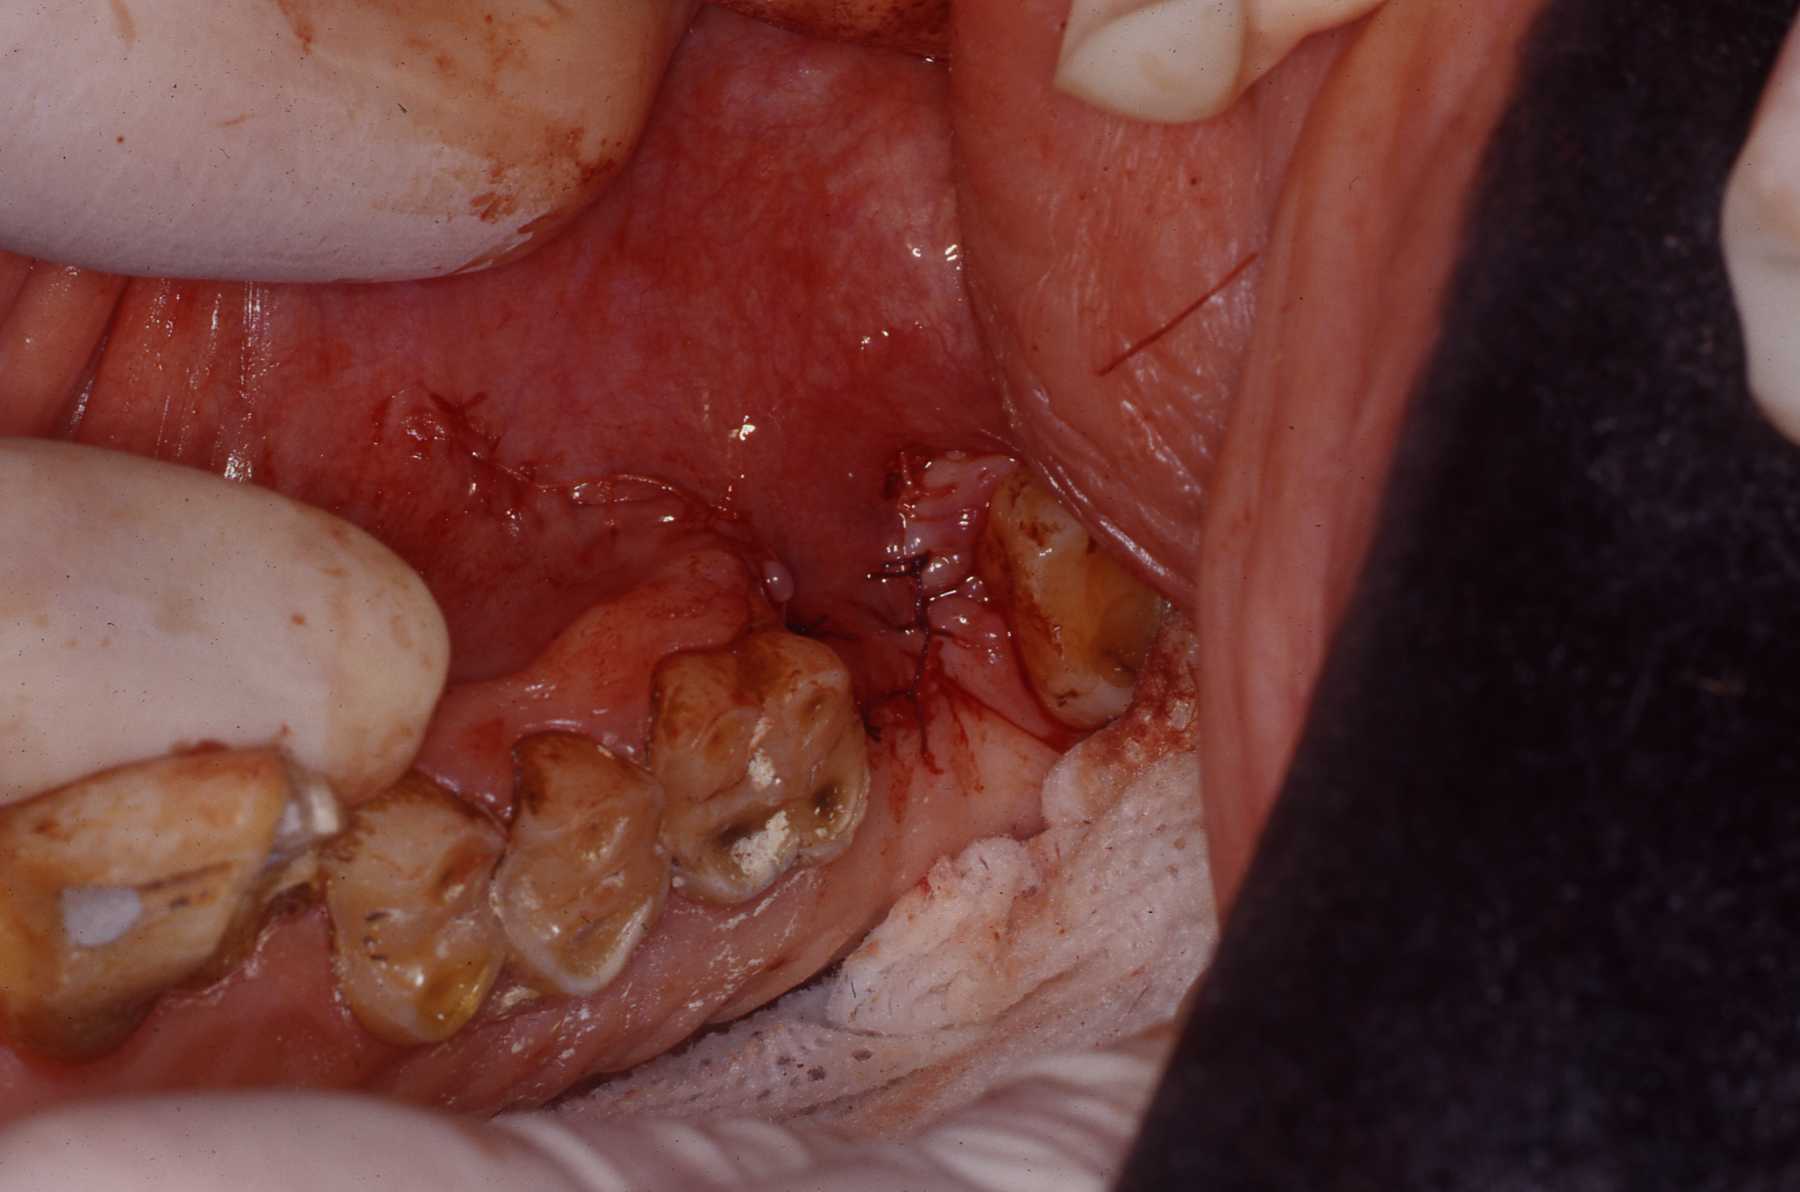

Alveoli after roots extracted

Extracted roots

Simple interrupted sutures placed with knots inside the wound so that Makanza will find it difficult to disturb them with his fingers and tongue.